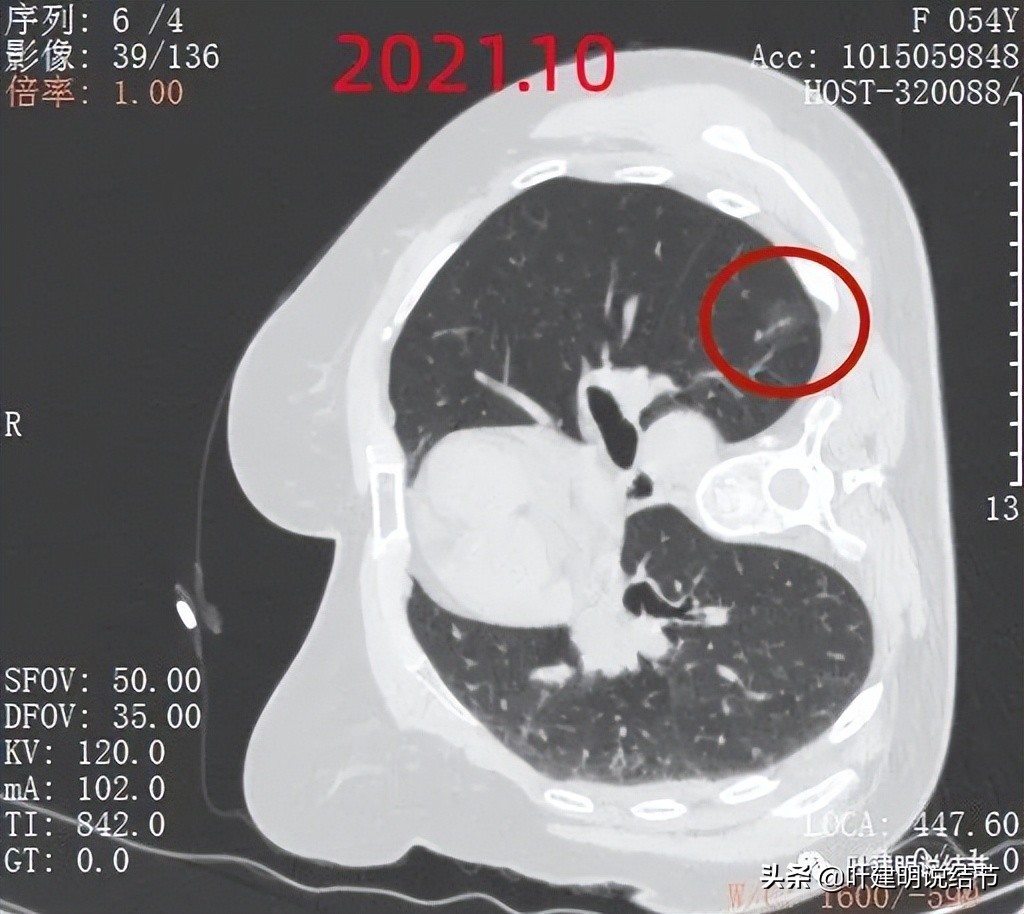

再来看2021年10月份的CT:

大病灶持续存在,没有吸收好转,考虑应该是肿瘤范畴的病灶,但因密度低,且无显著进展,仍可随访。

小病灶也是持续存在的,瘤肺边界清